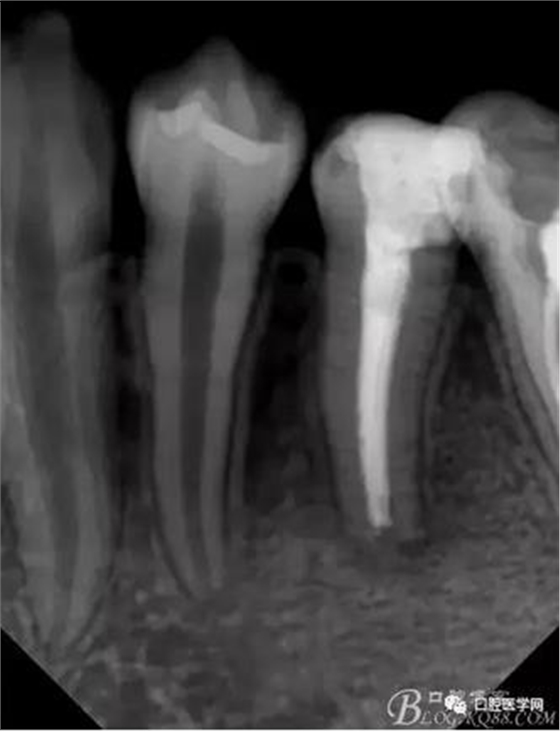

小心翼翼的控制根管長度后進行根管預備,3%雙氧水與生理鹽水交替沖洗,吸潮紙尖吸干,行氫氧化鈣根管充填,氧化鋅丁香油暫封,醫(yī)囑2周復診。

2周后 叩診(-)松動(-),去除暫封,生理鹽水沖洗掉氫氧化鈣,重新充填氫氧化鈣,氧化鋅丁香油暫封,醫(yī)囑1個月后復診。

一個月后檢查正常,再醫(yī)囑1個月復診。

一個月后因吃飯正常,無異常感覺,忘記復診。 電話通知復診,可還是再過了3周才復診。

去除暫封,生理鹽水沖洗,發(fā)現(xiàn)已經(jīng)形成根尖封閉,15#根管挫也無法通過根尖孔,忘記拍一張X片了。然后行根管充填。